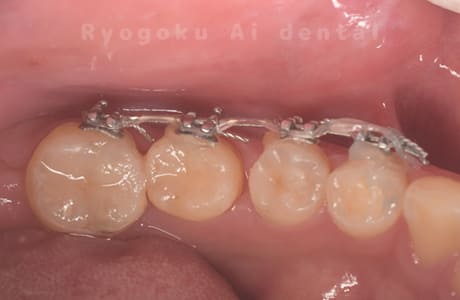

-

歯牙移植咬合面術前 -

移植する親知らず

歯牙移植術直後咬合面

歯牙移植術後咬合面

歯牙移植術前側面

歯牙移植術中側面

歯牙移植術後側面

部分矯正術前咬合面

部分矯正術中咬合面

部分矯正術後咬合面

部分矯正術前側面

部分矯正術中側面

部分矯正術後側面

- 原因

- 重度カリエス

- 治療内容

- 自家歯牙移植、部分矯正

- 治療費用

- 220,000円(移植費用)

110,000円(部分矯正費用)

虫歯が大きく、保存不可能となった歯を上の親知らずと交換する自家歯牙移植を行いました。移植歯が小ぶりであったため、部分矯正を行い問題なく噛み合い、経過良好です。